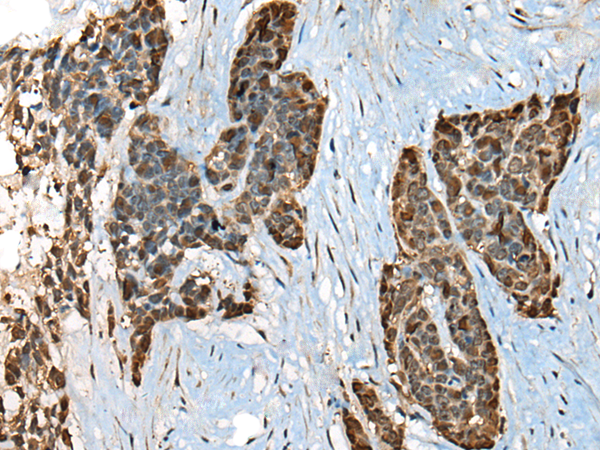

分类: 科研抗体货号: P09409别名: Kur; FBB18; CILD26; C21orf48; C21orf59应用: WB,IHC反应种属: Human, Mouse, Rat